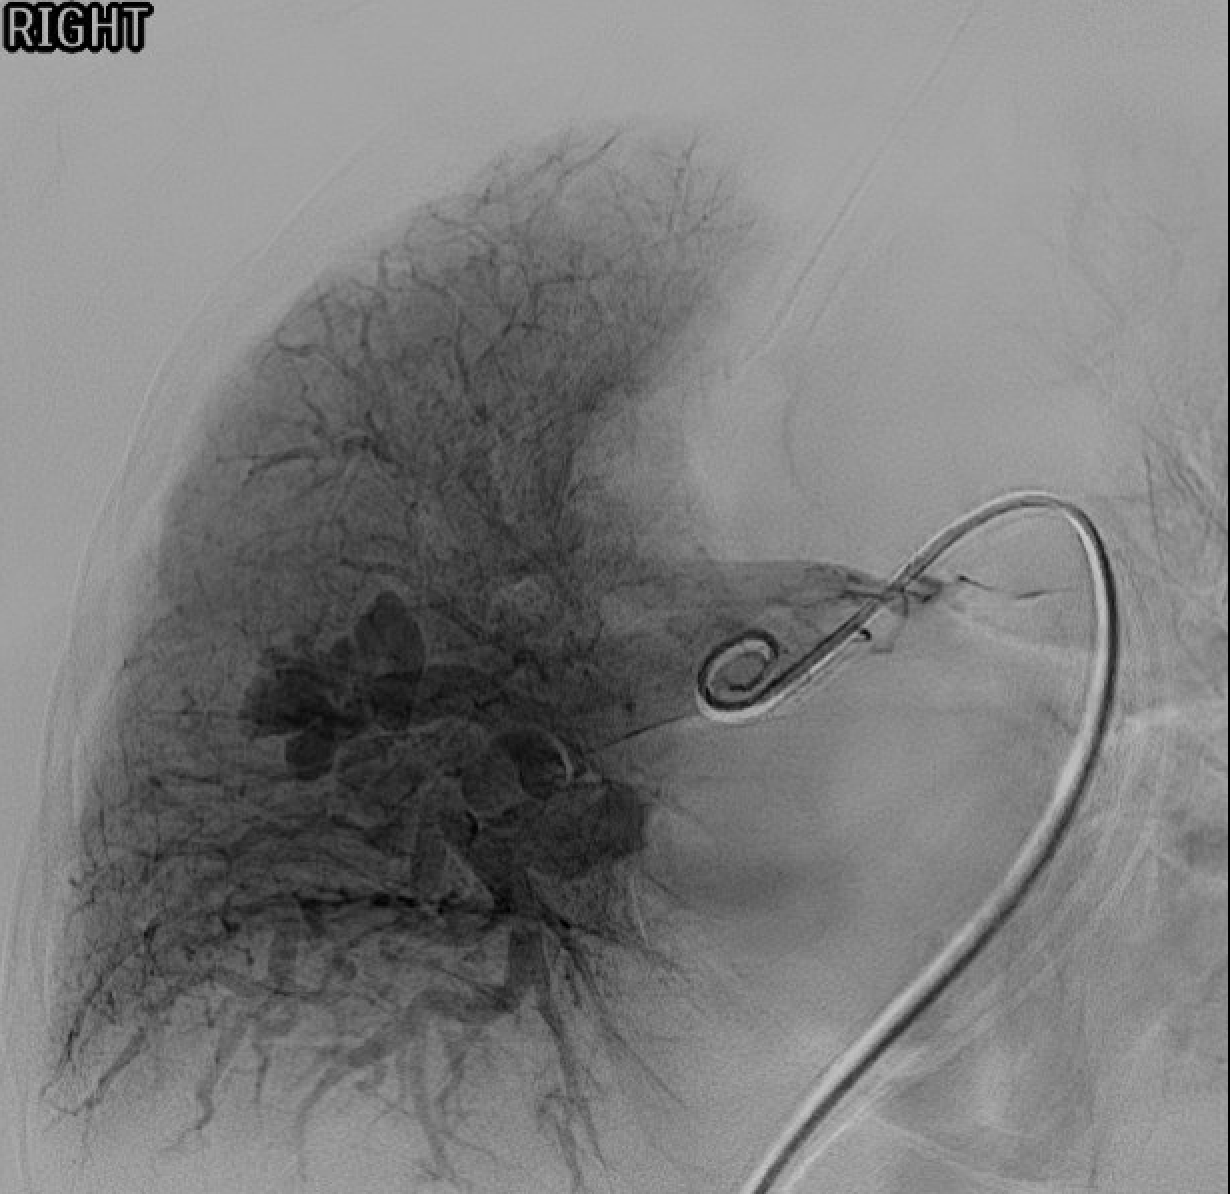

Pre-embolization pulmonary angiogram — contrast filling of the AVM sac via the feeding segmental artery.Post-embolization — coils in the feeding artery with stasis and no residual sac filling on completion angiogram.